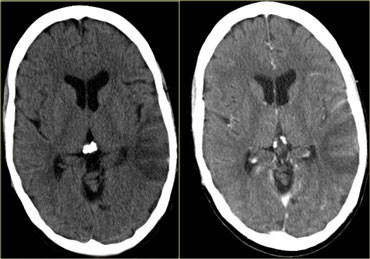

Dấu hiệu cục máu đông tăng tỷ trọng (2)

Hình ảnh tĩnh mạch vỏ não bị huyết khối biểu hiện dưới dạng một dải hoặc đường tăng tỷ trọng hình dây thừng còn được gọi là dấu hiệu dây thừng (cord sign).

Một thuật ngữ khác thường được sử dụng là dấu hiệu mạch máu tăng tỷ trọng (dense vessel sign).

Dấu hiệu cục máu đông tăng tỷ trọng (3)

Hình ảnh bên trái là của một bệnh nhân có nhồi máu xuất huyết ở thùy thái dương (mũi tên đỏ).

Lưu ý xoang ngang tăng tỷ trọng do huyết khối (mũi tên xanh dương).